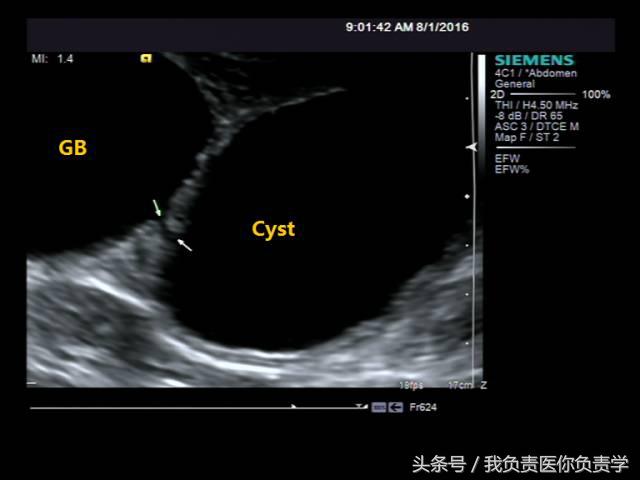

患者男,64岁,因右上腹疼痛半月余就诊。查体发现右上腹部轻压痛,无发热。超声检查所见如下:

图4和5为局部放大图像,可见胆囊与囊性回声区间可见直径约2mm的通道

超声检查考虑为胆囊炎合并胆囊穿孔,后经CT检查证实。